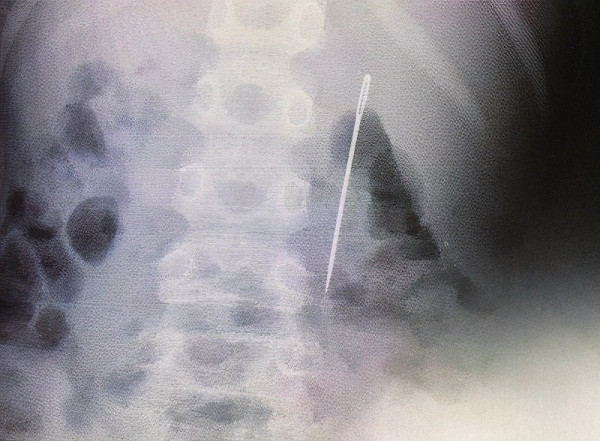

| Nuốt phải kim khâu song giấu mẹ, cậu bé suýt bị thủng ruột nghiêm trọng. |